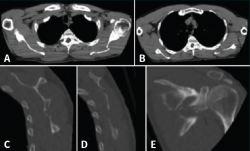

Presentamos el caso de un varón de 35 años, cerrajero de profesión y diestro. Sin antecedentes medicoquirúrgicos de interés. Sufre una caída desde un andamio de aproximadamente 2 metros de altura. Como resultado, es diagnosticado de una fractura de escápula en varios fragmentos, fractura del sexto arco costal derecho y una fractura no desplazada del ala sacra derecha. Las imágenes de la radiografía simple, de la TC y su reconstrucción 3D se muestran en las Figuras 3, 4 y 5.

Figura 4. A y B: corte axial; C y D: sagital; E: coronal de tomografía computarizada (TC).

Tras la realización del estudio de imagen obtuvimos unas medidas de 64 mm para el offset del borde lateral, un ángulo glenopolar de 27,5°, una angulación de la deformidad correspondiente a 12,9° (Figura 6) y, por último, una superficie articular conservada íntegramente, visualizada en los cortes y en la reconstrucción tridimensional de la TC.